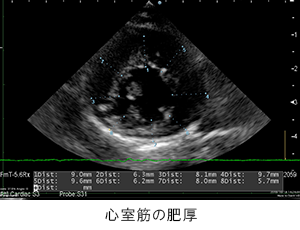

胸部レントゲン検査にて肺野の不透過性亢進像を確認。心臓超音波検査にて、心室筋の肥厚を確認。肥大型心筋症と診断。

胸部レントゲン検査にて肺野の不透過性亢進像を確認。心臓超音波検査にて、心室筋の肥厚を確認。肥大型心筋症と診断。